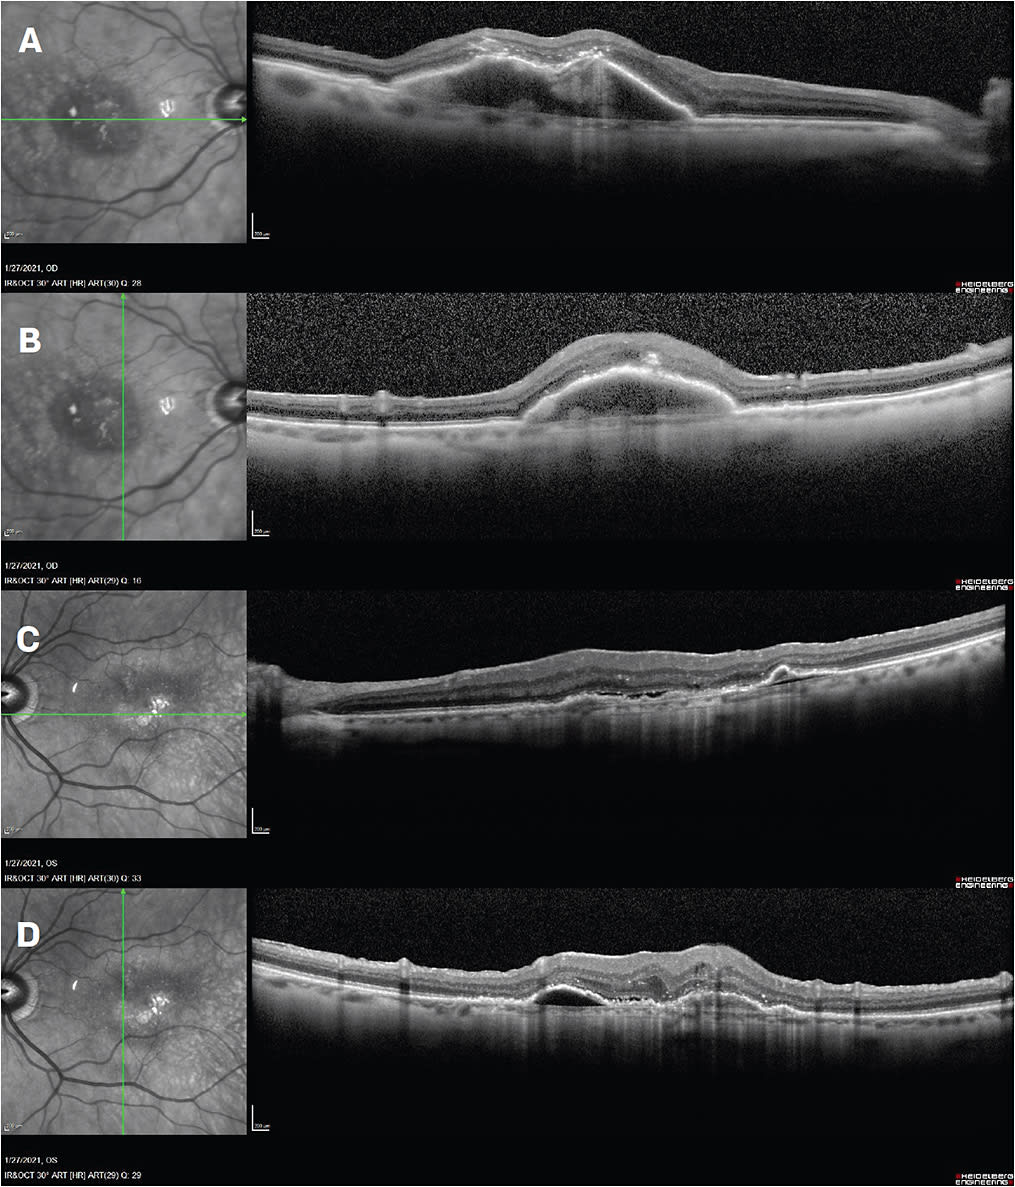

Dec. 30, 2020: The patient is 1 month from his last aflibercept injection OU. His vision is 20/50- OD and 20/100 OS. OCT OD shows a pigment epithelial detachment (PED) with intraretinal hyperreflectivity and trace SRF at the apex of the PED. OCT OS shows a shallow bilobed PED with significant SRF and mild IRF (Figure 1). The patient and I discuss the option of trying brolucizumab in his worse-seeing eye. We talk about the risk of intraocular inflammation and vascular occlusion associated with a small percentage of brolucizumab patients. He elects to proceed with aflibercept injection OD and brolucizumab injection OS.